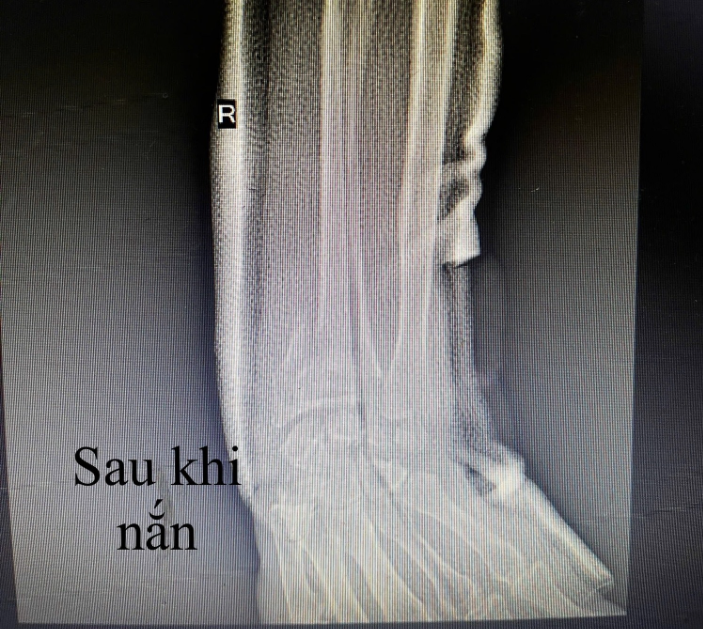

Tay bệnh nhân trên phim chụp trước và sau khi nắn - Ảnh BVCC

Sau thăm khám và tiến hành cận lâm sàng, các bác sĩ đã chỉ định: Nắn chỉnh trục xương - bó bột cố định đúng kỹ thuật.